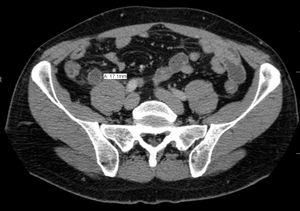

CT 스캔은 급성 충수염을 진단하는데 사용된다.[36] 의사는 환자의 병력과 증상을 평가하고, 신체 검사를 시행하며, 검사실 및 영상 검사를 모두 주문한다. 비전형적인 증상을 보이는 경우에는 초음파나 CT 스캔과 같은 영상 검사가 필요하다.[12] 소아는 방사선 노출 위험 때문에 초음파 검사를 우선적으로 시행하며, 결과가 불확실한 경우에만 CT 스캔을 추가로 시행한다.[54][55][56] 성인 및 청소년의 경우 CT 스캔이 초음파 검사보다 더 정확하며, 민감도 94%, 특이도 95%를 보인다. 반면 초음파 검사는 민감도 86%, 특이도 81%이다.[57]복부 초음파 검사, 특히 도플러 초음파는 특히 소아에게서 충수염 진단에 유용하다. 초음파 검사에서는 오른쪽 장골와에서 액체 저류, 컬러 도플러 사용 시 혈류 증가, 충수의 비압착성 등이 관찰된다. 급성 충수염의 다른 징후로는 충수 주변의 에코성 장간막 지방, 충수 결석의 음향 그림자 등이 있다.[58] 약 5%의 경우, 장골와 초음파 검사에서 이상이 발견되지 않지만, 이는 초기 충수염이거나 지방과 장내 가스로 인해 충수 확인이 어려운 성인에게서 흔하게 나타난다. 숙련된 검사자는 초음파 영상을 통해 충수염과 유사한 증상을 보이는 림프절 염증, 난소 또는 나팔관 문제 등을 구별할 수 있다.[60] 초음파 검사는 방사선과나 응급 의학 전문의가 시행할 수 있다.

컴퓨터 단층 촬영술(CT)은 병력 및 신체 검사에서 진단이 불확실한 경우에 자주 사용된다. 2019년 코크란 리뷰에 따르면 성인 급성 충수염 진단에 대한 CT의 민감도와 특이도는 높다.[62] 그러나 방사선 노출 우려로 인해 임산부와 어린이에게는 CT 사용을 제한하고, 자기 공명 영상(MRI) 사용이 증가하는 추세이다.[63][64]

충수염 진단은 충수 크기가 가장 중요하며, 6mm 이상이면 민감도와 특이도가 모두 95%이다.[65] 그러나 충수가 분변 물질로 채워져 팽창된 경우에는 진단이 어려울 수 있다.[66] 이 경우 초음파 검사가 유용하며, 주변 장에 비해 벽의 조영 증강, 주변 지방 염증 등의 특징으로 진단을 돕는다. 심한 경우 농성 염증, 고름집, 고름이나 장 내용물 누출로 인한 골반 내 액체 층이 관찰될 수 있다. 마른 환자는 지방 부족으로 충수와 주변 염증 관찰이 어려울 수 있다.[66]

CT 검사에서 충수 부종이나 주변 지방 조직 농도 상승이 관찰되며, 조영제 사용 시 민감도와 특이도가 모두 98%로 정확도가 높다. 최신 초음파 검사 장비는 맹장 형태 평가에 유용하지만, 맹장 위치나 장비, 검사자 숙련도에 따라 진단이 어려울 수 있다. 최근 소아 충수염 진단에서 컴퓨터 단층 촬영(CT) 검사는 감소하고 초음파 검사는 증가했지만, 임상 경과에는 변화가 없다는 보고가 있다.[126]